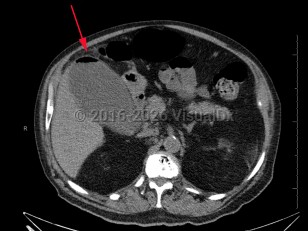

Emphysematous cholecystitis

Emphysematous cholecystitis is a rare variation of acute cholecystitis caused by secondary infection of the gallbladder wall with gas-forming bacteria such as Clostridium welchii, Clostridium perfringens, Escherichia coli, and Bacteroides fragilis as well as Pseudomonas, staphylococci, and streptococci. Men between the ages of 50 and 70 are most frequently affected. Type 2 diabetes and gallstones are common in affected patients. Emphysematous cholecystitis can also arise due to ischemia from atherosclerosis of the cystic artery.

Emergent antibiotic therapy followed by cholecystectomy is the treatment of choice due to increased risk of perforation.